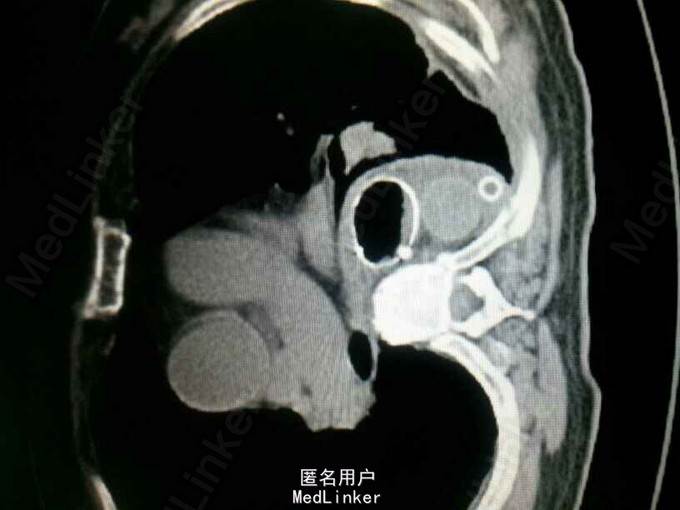

查体:气管居中,左肺呼吸音弱,右肺呼吸音尚可。未闻及湿啰音。胸腔引流管可见褐色浑浊液体引出。 腹部CT肝脾胰未见异常,胆总管扩张。 食管造影:食管下端撕裂,食管胸膜瘘。 胸CT左肺气胸,左侧胸腔内高密度影,考虑造影剂漏入胸腔。左肺实变,右侧少量胸腔积液。

诊断:自发性食管破裂。 治疗:急诊行胸腔闭式引流。后行左剖胸食管破裂修补。术中见胸腔污染严重,见菜叶,消化液等。后纵膈可见较多脓性分泌物,食物残渣,坏死组织。食管裂口处上方可见5cm纵向肌层及粘膜层撕裂口,相应位置处可见纵膈胸膜撕裂口。术后予肠内肠外营养,舒普深,泰能,稳可信,抗感染,术后反复行2次食管造影,仍存在食管破裂口,术后一月行胃镜及食管支架植入术。第二天行进食流质及半流质通畅,平稳出院。